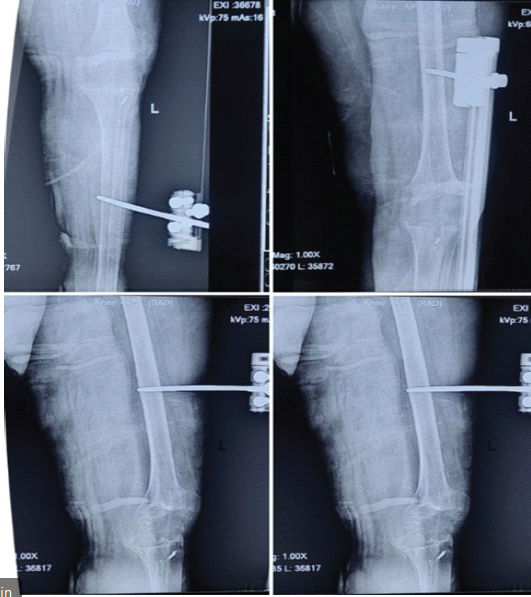

After completion of 6 weeks of antibiotic therapy and a planned 3-week infection surveillance period, Stage II was undertaken. Although ESR and CRP had normalized, definitive reimplantation was deliberately deferred due to the presence of a chronic sinus tract, compromised soft-tissue envelope, and significant bone loss, placing the patient at a high risk of reinfection with immediate reimplantation.

A limb reconstruction system (LRS) external fixator was applied to maintain limb length and alignment while avoiding the introduction of internal hardware that could serve as a nidus for persistent infection (Fig. 3).

Figure 3: Anteroposterior and lateral radiographs following the antibiotic cement spacer exit and fixation with the limb reconstruction system external fixator, maintaining joint alignment and limb length.

During this stage, the patient received an additional 3 weeks of culture-directed oral antibiotics. Partial weight bearing was permitted, and the patient was monitored clinically and biochemically for signs of recurrent infection.

The interval between Stage II and Stage III was 3 weeks. The total duration of six weeks of systemic antibiotic therapy following implant removal is consistent with recommendations for staged revision in prosthetic joint infection. [14]